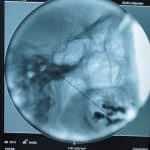

- Rizotomia percutânea lombar

- Rizotomia percutânea trigeminal

- Bloqueios anestésicos

- Neurólises químicas e cirúrgicas